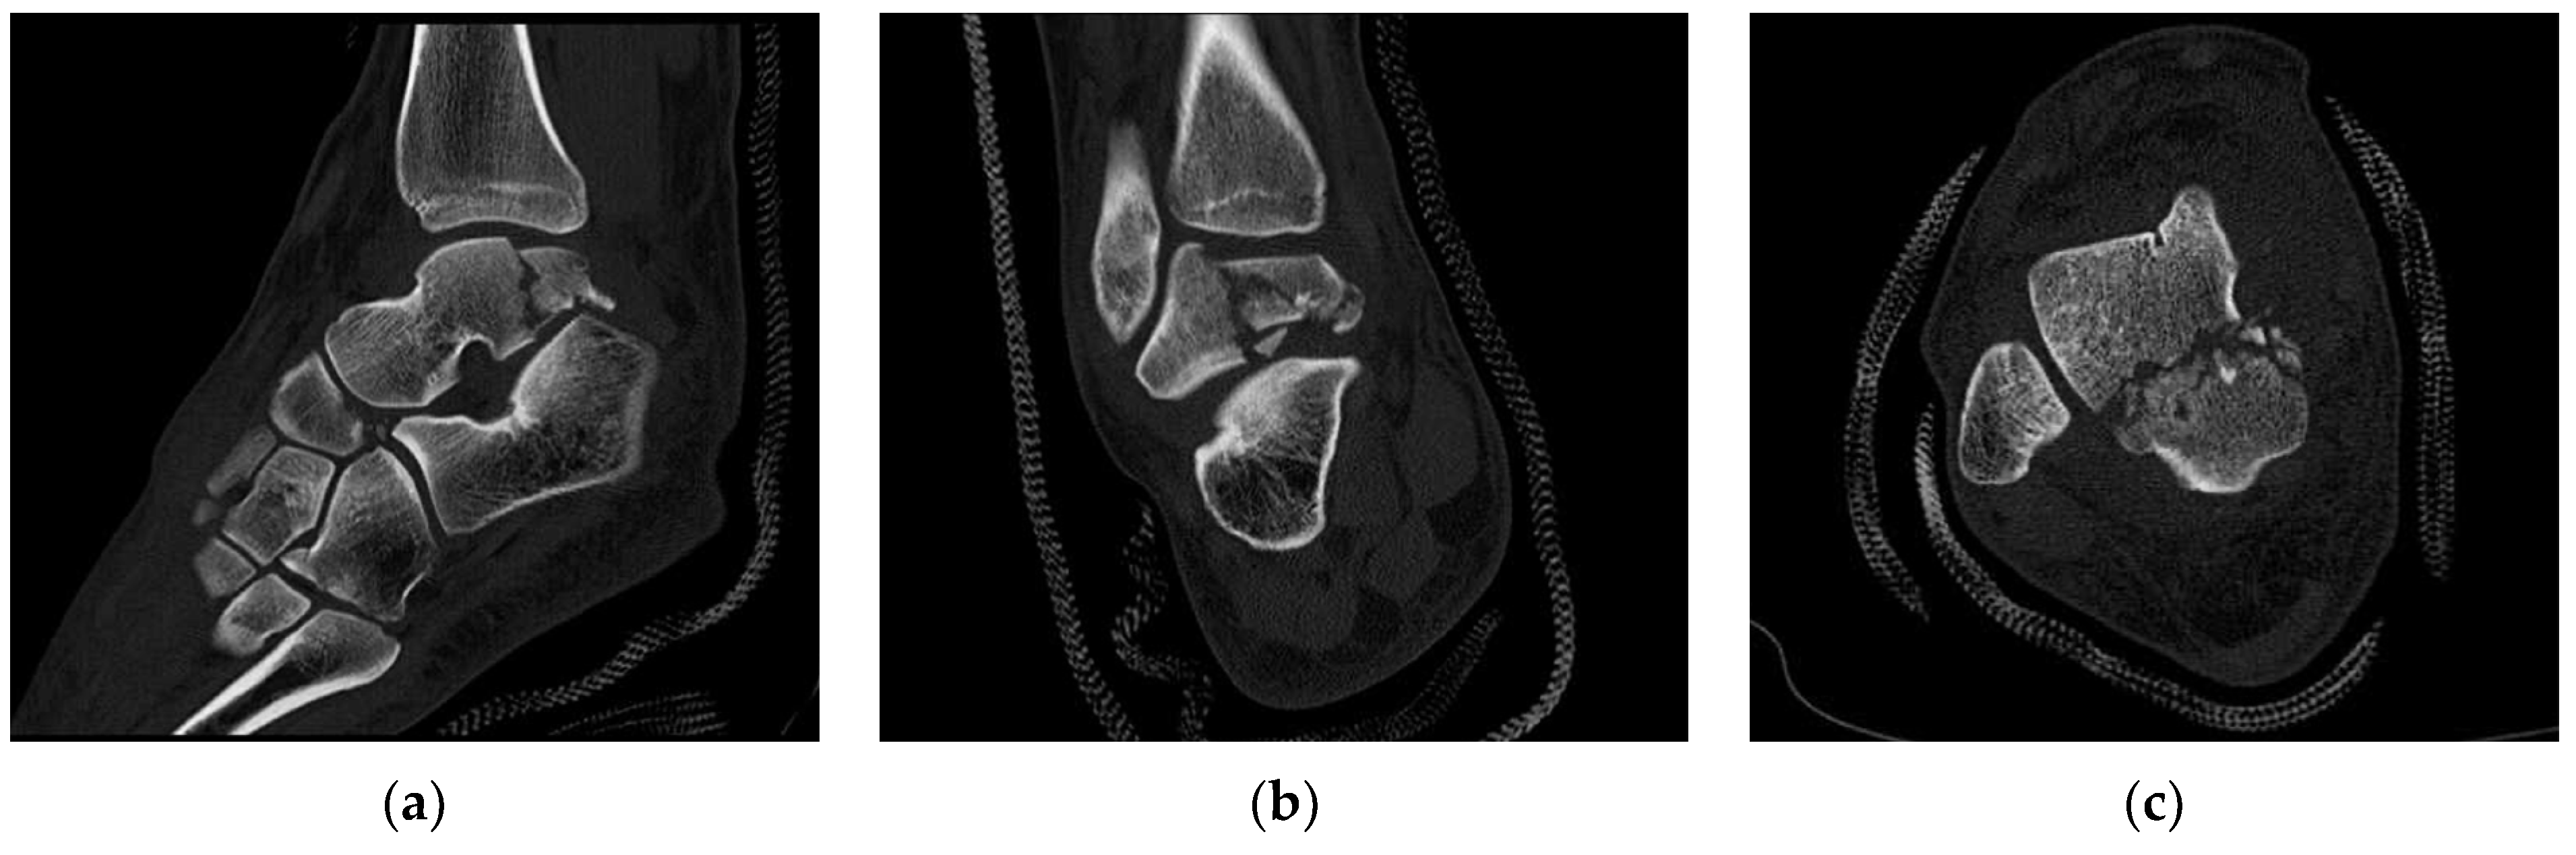

Osteology Free FullText Talus Fractures in Snowboarders A Case Series Talus Bone Death Both traumatic and atraumatic causes have been implicated in talar avn. Displaced talar fractures are responsible for about 75% of avascular necroses (avns) that only affects part of the talar body in a substantial percentage of cases. Avascular necrosis is a painful bone condition that causes bone tissue death. This condition is called avascular. Talar avascular necrosis happens when the. Talus Bone Death.